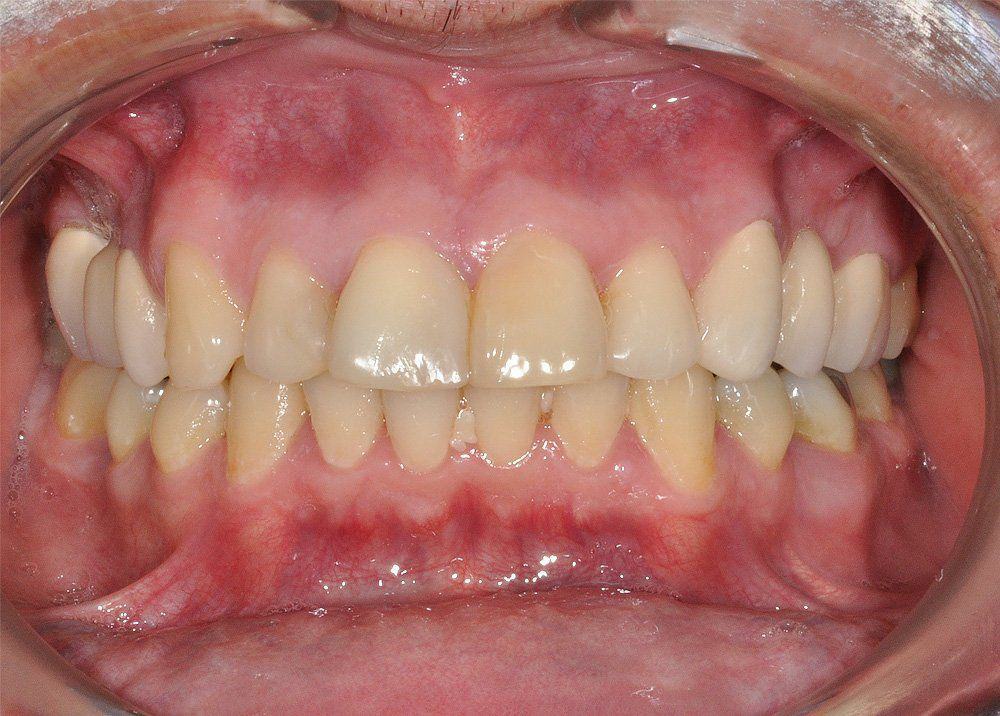

Reporte del Caso: Paciente sexo masculino, 36 años, con diagnóstico de esquizofrenia y trastorno bipolar en tratamiento. Consulta por el recambio de dos prótesis fijas plurales (PFP) de reemplazo de dientes 4 y 13 con pilares en piezas 3, 5, 12 y 14 mediante rehabilitaciones unitarias de los dientes pilares y reemplazo mediante implantes en zonas edéntulas.

El estudio imagenológico evidencia una pérdida ósea severa en altitud y grosor, situación que complejiza la colocación de un implante. Se analizan alternativas de tratamiento y se opta por una vestibuloplastía mediante autoinjerto conectivo de mucosa palatina que se reposiciona sobre la zona del defecto óseo. Además se realiza retratamiento de ambas PFP, ahora en zirconia, por motivos estéticos y oclusales. Se realizan controles posteriores para evaluar la respuesta gingival a la vestibuloplastía.

Conclusiones: La ausencia de un diente no siempre es indicativo de implante. El tratamiento elegido debe tener las menores complicaciones, el mínimo daño, el máximo beneficio y un costo económico de acuerdo a la realidad del paciente. La PFP de zirconio y la vestibuloplastía son alternativas de tratamiento efectivas para la resolución de defectos óseos por ausencia dentaria en la cavidad oral.